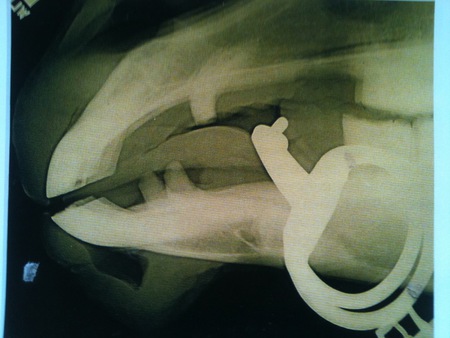

Správne zvolené a používané zubadlo je aj správne umiestnené. Každé nepohodlie koňa, spôsobené zubadlom, vychádza z jeho vulgárneho alebo nesprávneho používania. Takéto zubadlo koňa tlačí a môže sa mu dokonca dotýkať zubov, čo je nemožné, pokiaľ jazdec nepôsobí rukou výrazne dozadu alebo pokiaľ nemá kôň hlavu v nesprávnej pozícii (tzn. za kolmicou). Na obrázku je kôň na normálnom kontakte. Pokiaľ jazdíte správne a nenutíte koňa nosiť hlavu za kolmicou, zubadlo sa zubov nebude dotýkať a predídete mnohým problémom.

Zdroj obr. 1: The effects of the bit